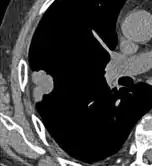

For cases suspicious enough to proceed to biopsy, small biopsies can be obtained by fine needle aspiration or bronchoscopy are commonly used for diagnosis of lung nodules.[19] CT guided percutaneous transthoracic needle biopsies have also proven to be very helpful in the diagnosis of SPN.[6]

In selected cases, nodules can also be sampled through the airways using bronchoscopy or through the chest wall using fine-needle aspiration (which can be done under CT guidance). Needle aspiration can only retrieve groups of cells for cytology and not a tissue cylinder or biopsy, precluding evaluation of the tissue architecture. Theoretically, this makes the diagnosis of benign conditions more difficult, although rates higher than 90% have been reported.[20] Complications of the latter technique include hemorrhage into the lung and air leak in the pleural space between the lung and the chest wall (pneumothorax). However, not all these cases of pneumothorax need treatment with a chest tube.[21]